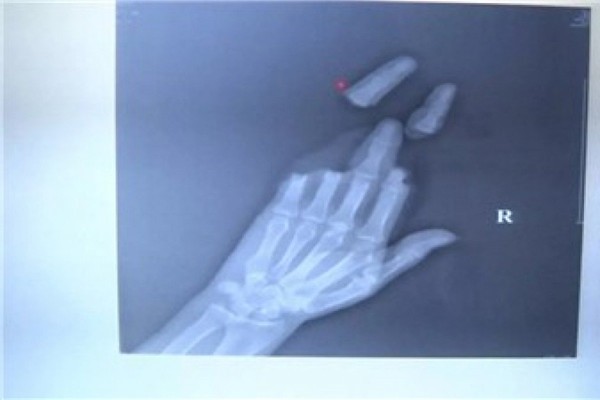

Ảnh chụp X-quang 3 ngón tay bị dây diều cắt đứt.

Jin Dejun, giám đốc Khoa phẫu thuật chân tay của bệnh viện chỉnh hình Nam Thông cho biết, khi nam thanh niên đến đây, ngón tay thứ 2 đến ngón tay thứ 5 đều bị cắt đứt.

Tuy ngón giữa không bị đứt lìa ra nhưng đó chỉ là các phần xương kết nối với nhau, trong khi dây thần kinh và gân cơ đều đã bị cắt đứt.